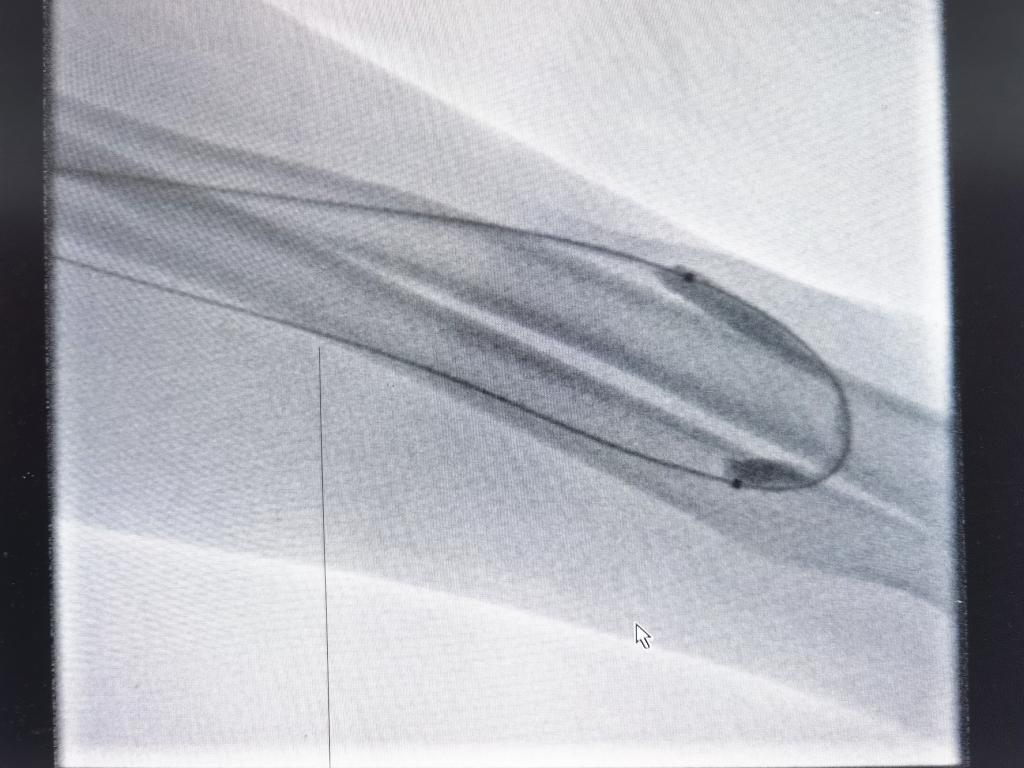

随后我们将球囊置入到狭窄位置,加压发现球囊“有腰”这是狭窄的典型表现: